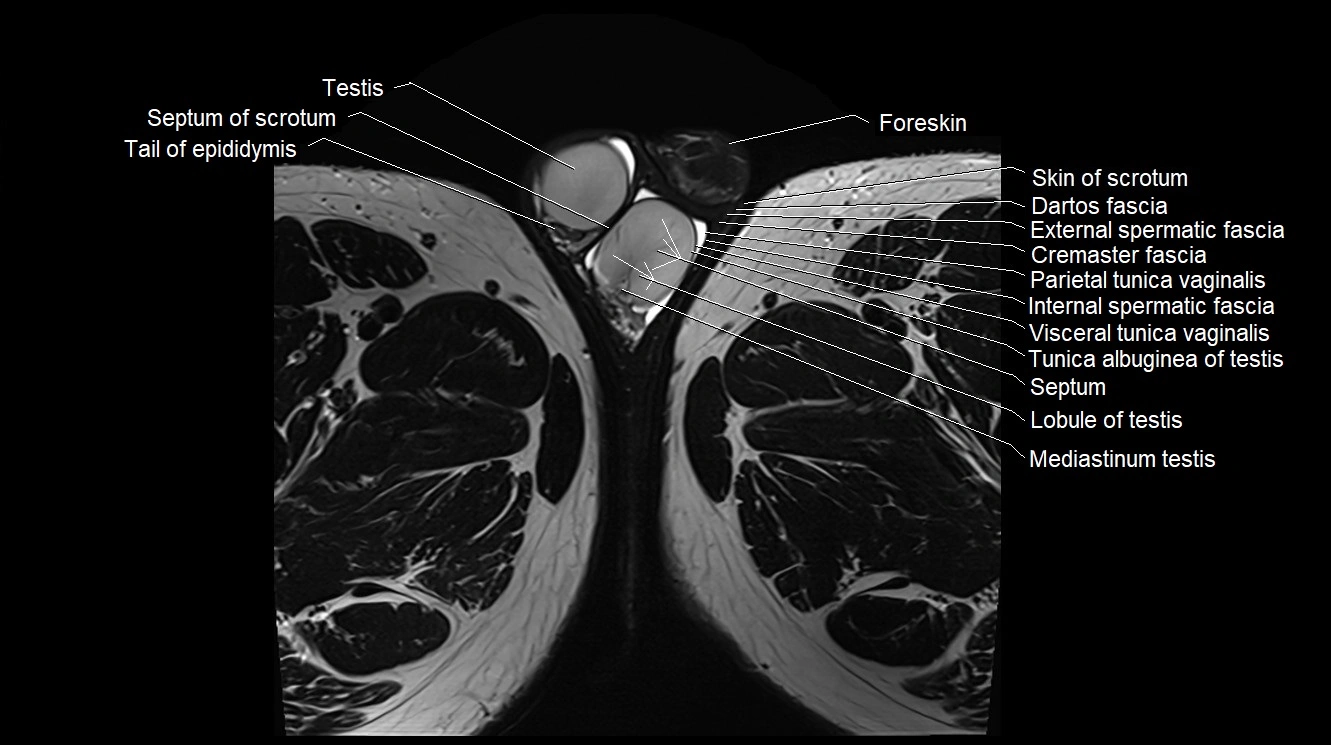

MRI image